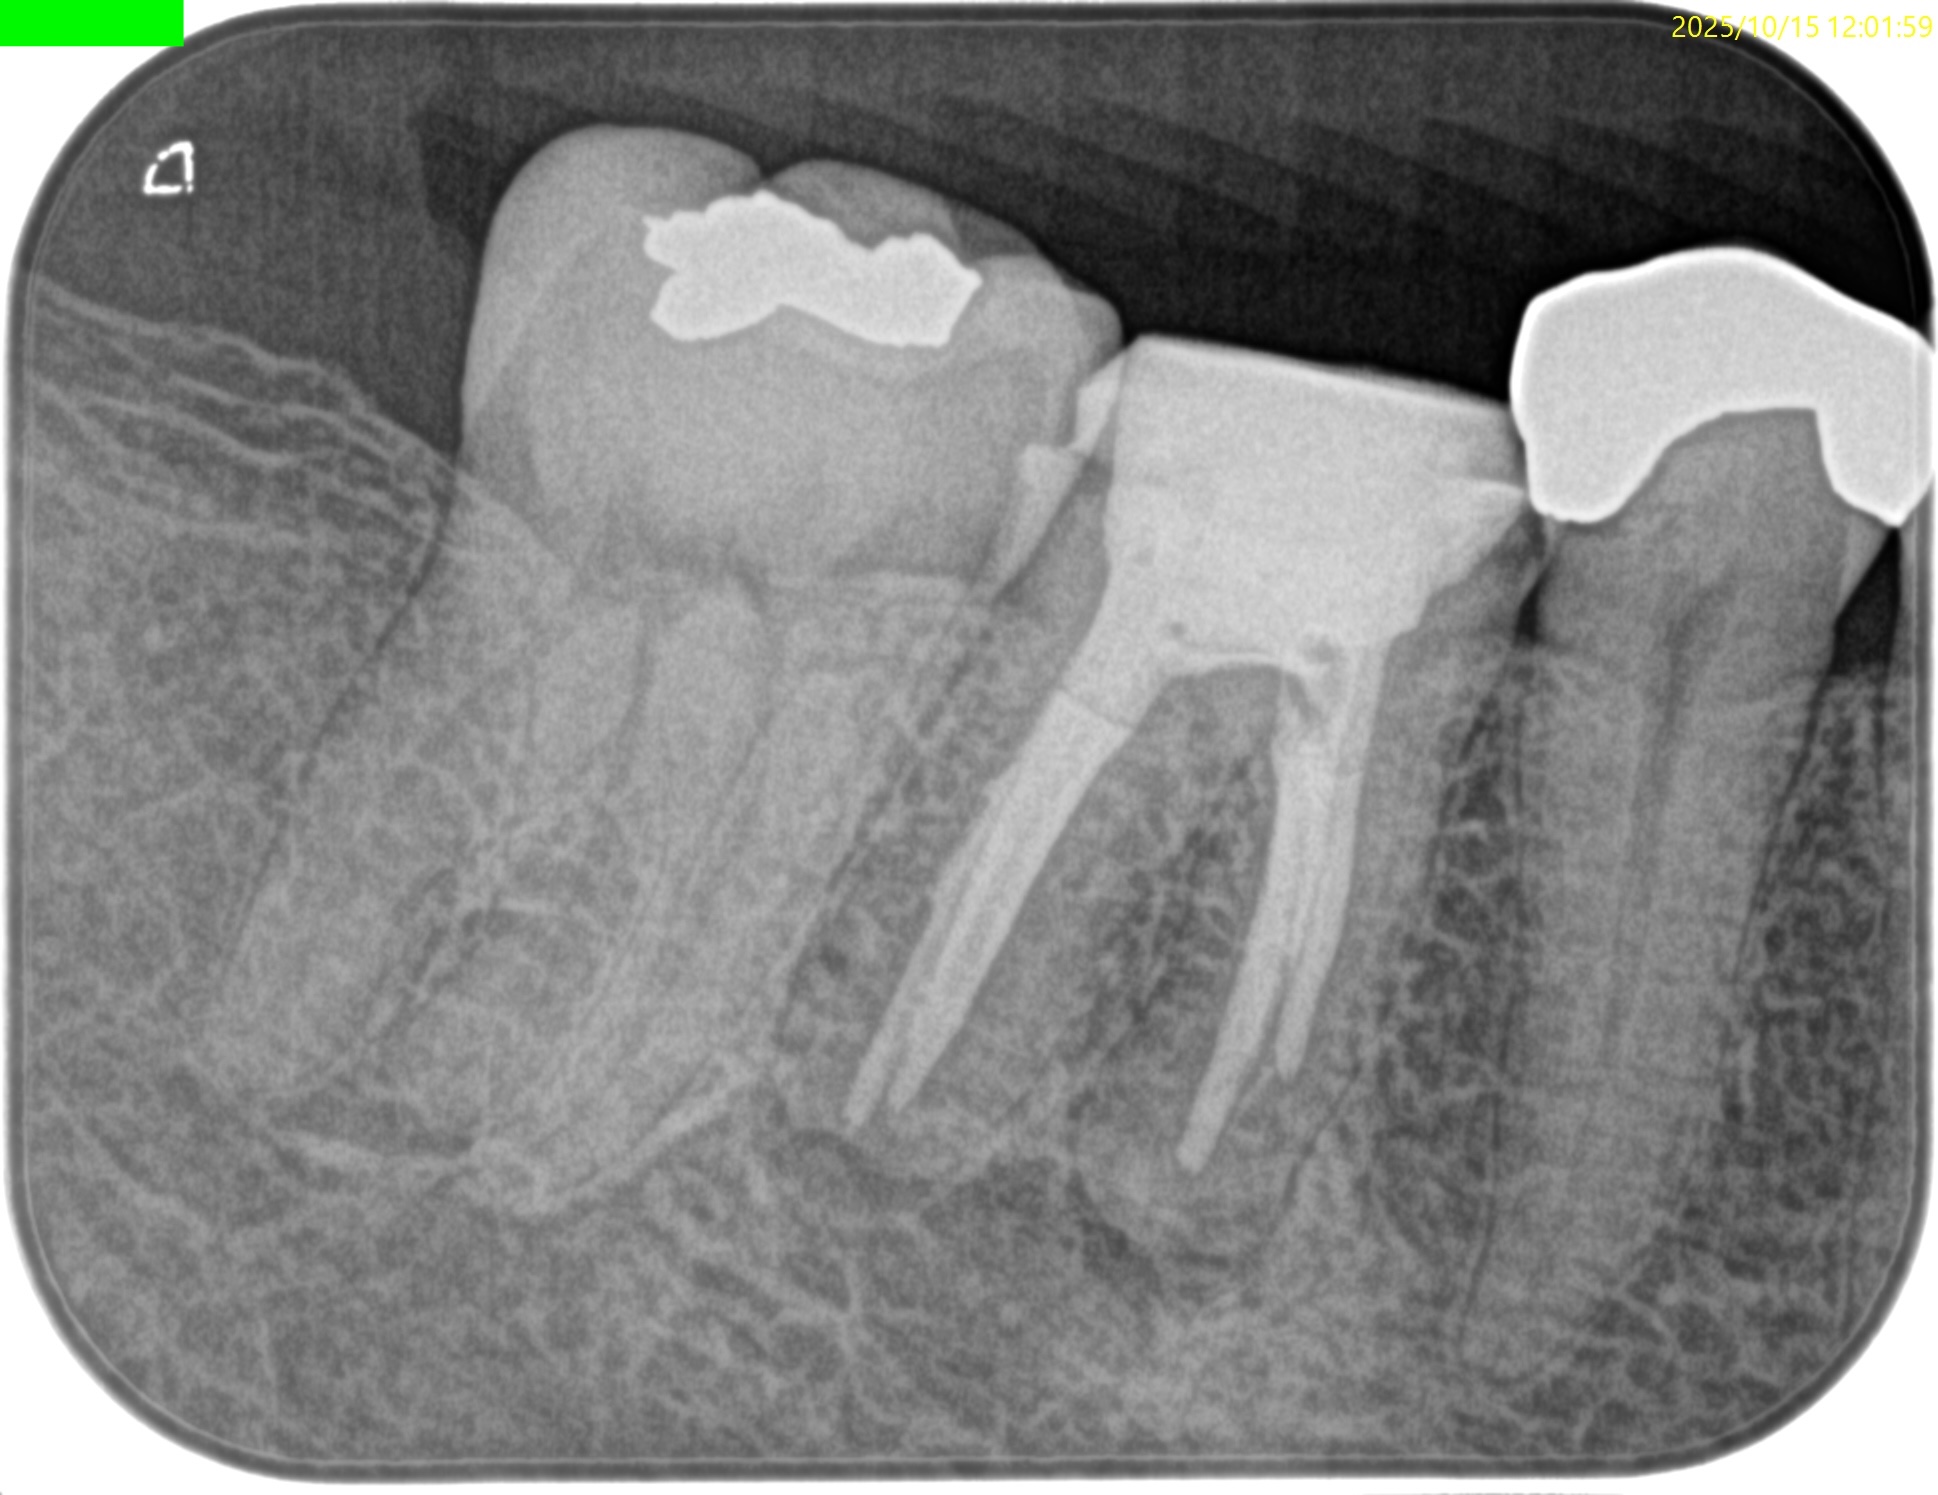

PA(2025.12.2)

#30 Cold N/A, Perc.(+), Palp.(+), BT(++), Perio Probe(WNL), Mobility(WNL)

#30が患歯のようだ。

M,Dの根尖部には病変がある。